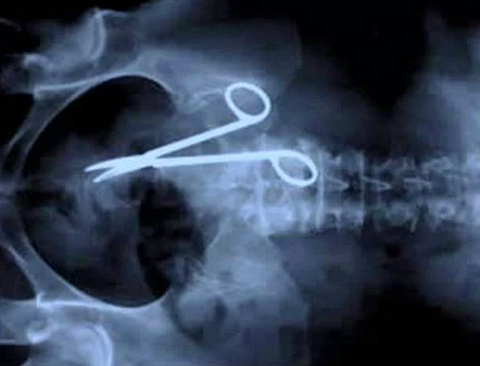

Diş Ağrısından Fazlası Bu Xray'in sahibinin o çiviyi oraya sokmasından daha ilginci, diş ağrısı sebebiyle dişçiye gittikten sonra orada bir çivinin olduğunu farketmesi.. Sürpriz evlenme teklifi Amerikalı bir adam, sevgilisine sürpriz yapmak için aldığı tektaş yüzüğü kızın milkshakeinin içine koyuyor.. Bu da sonucu Kafaya saplanan bıçak Silahlı soygun kurbanı bu arkadaş, tamamen iyileşmiş Ameliyatta makas unutma klasiği Kafada ok! Çin'de şakalaşırken arkadaşı tarafından kafasından okla vurulan çocuk. Neyse ki bu da iyileşmiş Kürdan niyetine makas Bu Çinli arkadaş da, dişinin arasına kaçan şeyi ufak makasla almaya çalışırken arkadaşları tarafndan güldürülünce yutuvermiş makası.. Kafasına Bıçak Giren Asker Tam gözünün üstünden kafasına yaklaşık 7 cm içeriye kadar bıçak girmiş olmasına rağmen bu asker de hasarsız bir şekilde hayata dönmüş.. Kafaya birşey girince ölünmüyor galiba !?! Makatta Ampul.. Hem de tersten :( Bu fantastiklik de Pakistan'dan.. Kolonda Cep Telefonu San Salvador'da bir hapishaneden.. İçeri cep telefonu sokmak için.. Kafaya Matkap Matkapla çalışırken merdivenden düşen inşaat işçisinin Xray görüntüsü.. O da hayatta! Yüzde Anahtar! 17 aylık çocuk Nicholas Holderman, bir şekilde annesinin anagtarlarını burnundan ve gözünden içeri sokmuş.. O da tamamen iyileşmiş! Dev böbrek taşı! İster inanın, ister inanmayın bu böbrek taşı Macaristan'daki bir hastanın içinde bulundu! Top Mermisi Evet top mermisi bir askerin makatında bulunuyor. İşin komiği ameliyat esnasında mermi yanlışlıkla patlamasın diye uzman bir ekip bulundurulmuş.. Çatal! İsrailli bir kadın yanlışlıkla yemek yerken hamam böceği yutuyor. Çıkartmak için de çatal kullanmaya çalışırken, onu da yutuyor.. Gerçekten insanların hiç farkında olmadan beyinlerine çivi saplayabilmesi çok acayip. Güney Kore'li bu adam da, başağrısı şikayetiyle doktora gelip beyninde bir çivi farkediyor İntihar bombacısının midesinde el bombası İntihar bombacılarının beynini yıkadıklarını biliyorduk da, bununkini fazla yıkamışlar galiba Sandalye Bacağı Shafique El-Fahkri isimli genç, barda kavga etmeme konusunda ders almış. 20 yaşındaki Liam Peart'ın attığı sandalye bu şekilde gözünden girip boğazına kadar gitmiş. Bu arkadaş da ölmemiş..